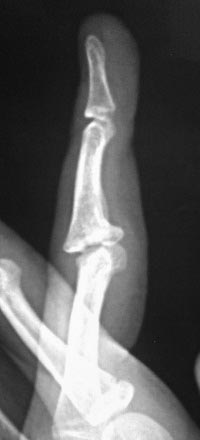

Неправильно сросшийся эпифизиолиз средней фаланги пальца кисти. Разгибательная контрактура Нужен ваш совет. Случай неординарный

Девочка 14 лет. В июле 2016 года ударила палец о мяч. Лечились гипсовой иммобилизацией 4 недели и всё. Обратились через 5 месяцев, с жалобами на сохранившееся ограничение сгибания.

При осмотре: сгибание в проксимальном межфаланговом суставе 3 пальца кисти на 90 градусов.

На рентгенограммах: фрагментарный перелом волярой части эпифиза со смещением на первичных снимках, сохранившееся (усилившееся) через 5 месяцев. Состояние подвывиха.